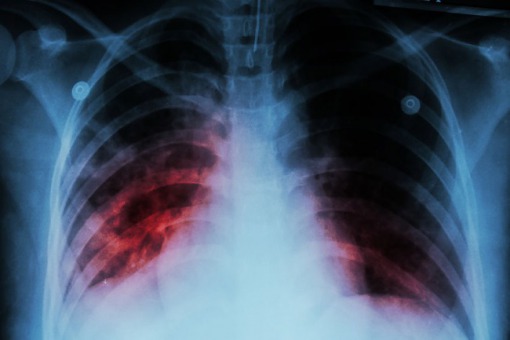

Co Koronawirus Robi Z Plucami Wstrzasajace Zdjecia Wloskich Lekarzy

Szokujace Zdjecia Pluc Ofiary Koronawirusa Super Express Wiadomosci Polityka Sport